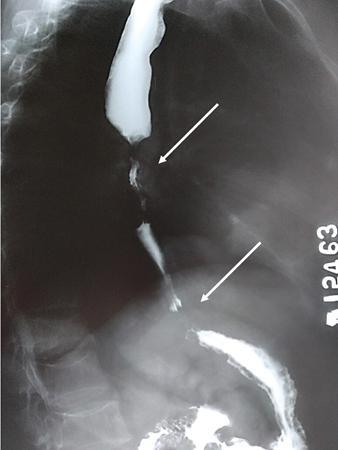

Fig. 7.4.2.1Barium swallow in a 50-year-old male with history of progressive dysphagia of one-year duration. Source: (Image courtesy Dr Vijinder Arora, Nijjar Scan & Diagnostic Centre, Amritsar, India.) Radiological Technique: Barium swallow (barium pharyngography).

A barium-filled outpouching is seen posterior to the cervical oesophagus, with the neck of the pouch at the level of C5–C6 (just cranial to the anticipated position of the cricopharyngeus muscle).

Principal Diagnosis: Zenker’s diverticulum.

Pharyngeal/oesophageal pouches and diverticula are mucosal protrusions through weaknesses in the muscular pharyngeal wall. Pouches are transient and diverticula are permanent. Based on their aetiology, they can be classified as pulsion, traction or developmental. Based on location, cranial to caudal, these are:

• This is an acquired condition due to adhesions formed with subcarinal or perihilar lymph nodal disease (like tuberculosis).

• They usually occur in the midoesophagus, triangular in shape with pointed tip and a wide neck.

• Traction diverticulum tends to empty when oesophagus is collapsed as walls have muscle.

• Similar lesion may be seen due to oesophageal dysmotility (pulsion diverticulum).